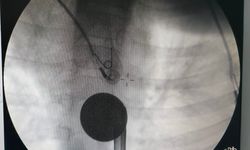

Diyarbakır'ın Ergani ilçesinde yaşayan Kızmaz ailesi, gebelik sürecinde 2021 yılında Diyarbakır merkezde bulunan özel bir hastaneye başvurdu. Hamilelik süreci içerisinde aynı doktora muayene olan aile 3 Temmuz 2021'de Ergani Devlet Hastanesinde çocuklarını kucaklarına aldı. Çocuklarının Down Sendromlu olduğunu hemşireden öğrenen aile, mutluluk ve hüznü bir arada yaşadı. Doktorların hamilelik sürecinde kendilerine bilgi vermediğini ve teste almadığını iddia eden aile, Diyarbakır'daki özel hastane ve doktordan şikayetçi oldu. Avukat Ferhat Yiğit'e giden aile dava açılması için işlemlerin başlatılmasını istedi. Arabuluculuk sistemi üzerinden iletişime geçilen hastaneden 700 bin lira talep eden ailenin isteği reddedilince Ergani 1'inci Asliye Hukuk Mahkemesinde dava açıldı. Dava geçtiğimiz aralık ayında karara bağlandı. Mahkeme, aileyi haklı bularak doktoru 43 milyon lira tazminat ödemeye mahkum etti. Geçen süre göz önüne alınarak yasal faiz ve yargılama ücreti ile birlikte bu rakam 81 milyon liraya yükseldi. Hastane, karara itiraz ederek durumu üst mahkemeye taşıdı.

Konu ile ilgili açıklamalarda bulunan ailenin avukatı Ferhat Yiğit, iki haftadan bu yana gündemi meşgul eden Down Sendromlu çocuk davası olarak yanlış bilinenleri açıklamak istediğini söyledi. Yiğit, ''İki hafta önce, davamız karara çıktıktan sonra, bazı hekim sendikaları davamızla alakalı toplumu, kamuoyunu yanlış bilgilendirecek düzeyde bilgiler paylaştılar. Bu paylaşımlar içerisinde özellikle mağdur ailemizi rencide edecek karikatürlerden de bahsettiler, paylaşım yaptılar. Biz de buna ilişkin sosyal medyada gerekli cevapları verdik. Akabinde kendileri ulusal basını da kullanarak vermiş oldukları yanlış bilgileri tekrarlamaya çalıştılar. Bize de cevap hakkı doğdu. Bu davamızı 2021 yılının 10'uncu ayında açtık. Dava açmadan önce zorunlu arabuluculuk sisteminden kaynaklı olarak taraflara ulaştım, 700 bin liralık bir teklifle gittik kendilerine. Taraftar bu teklifimizi kabul etmedi, davamız 2021 yılının 10'uncu ayında açıldı, 2025 yılının 12'nci ayında da karara çıktı. Hekimin aydınlatma yükümlülüğü ihlal ettiği yönünde karar çıktı. Hekim muayeneye giden aileye hiçbir suretle tarama testi önermedi, yazılı bir onama almadı, aydınlatma hükümlülüğünü ihlal ettiği için de gebe müvekkilimize gebeliğin sonlandırma seçeneği hakkı tanımadı. Bundan kaynaklı da ailemiz çocuklarının sağlıklı olduğunu düşünerek doğumu gerçekleştirdi. Doğum esnasında çocukların Down Sendromlu olduğunu öğrendiler. Biz de hastanede ilgili raporlarını aldık, incelediğimizde tarama testi verilmemişti, davamız bu şekilde görüldü, bu şekilde karara çıktı. Miktarı basında 77 milyon lira olarak geçti lakin şöyle bir durum var, dava 43 milyon lira üzerinden karar çıktı. Bunun dışında 26 milyon lira bir faiz işlemiş, faizi vardı, birkaç yargılama masrafı, icra harçları ve vekalet ücretleri dahil edildiğinde şu an güncel borç miktarı 81 milyon liradır. Dava üst mahkeme aşamasında, davamız devam ediyor. Biz bağımsız yargının vereceği her karara saygı duyacağız, hiçbir şekilde toplumu yanlış bilgilendirmedik bilgilendirilmesini de istemiyoruz aile hakkında bizim hakkımızda davanın hakimi hakkında çirkin ithamlardan bulunan herkese karşı da zaten suç duyurusunda bulunduk bulunmaya da devam ediyoruz bu dosya emsal nitelikte bir dosyadır o yüzden üst mahkemenin vereceği kararı biz de merakla bekliyoruz'' dedi.